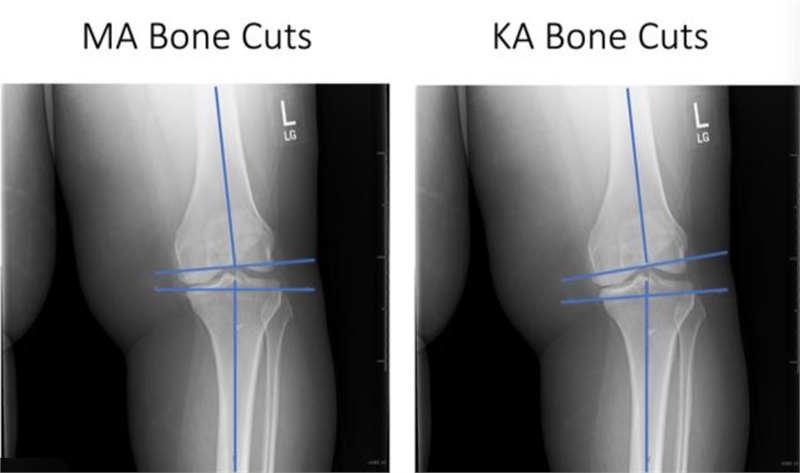

강철병원이 전면에 내세우는 핵심은 **로봇 인공관절 수술 시스템 ‘ROSA’**를 활용한 정밀 수술이다. 이는 기존 기계적 정렬(MA) 방식처럼 관절을 일직선으로 맞추는 데 그치지 않고, **환자 고유의 관절 움직임을 살리는 운동학적 정렬(KA)**을 구현하는 데 목적이 있다.

조수현 대표원장(정형외과 전문의)은 “최근 인공관절 수술의 트렌드는 단순히 통증을 줄이는 것이 아니라, 수술 전처럼 자연스러운 움직임을 회복하는 데 있다”며 “관절 주변 인대와 힘줄의 균형을 얼마나 정밀하게 유지하느냐가 수술 결과를 좌우한다”고 설명했다.

특히 로봇 수술은 미세한 각도와 압력 차이를 수치로 확인하며 수술할 수 있어, 환자별 맞춤 수술이 가능하다는 점에서 의미가 크다.